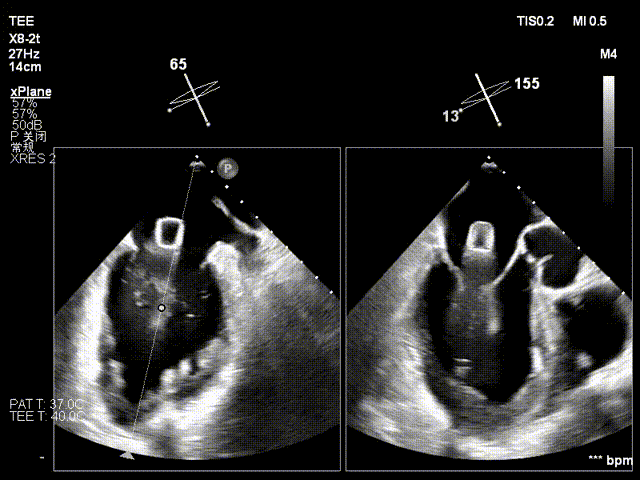

术前心超提示:

退行性二尖瓣反流(DMR),A2-A3脱垂伴连枷样运动(脱垂范围:17mm,连枷间距:7mm),P3脱垂,反流主要位于2-3区,MR重度4+(VC:6*17 mm),A3:18mm,P3:9mm,A2:24mm,P2:14mm,AP:32mm,二尖瓣口面积MVA约 5.6cm²,左房、左室明显扩大。

术中操作(关键步骤超声)

在全麻下,于心尖入路完成ValveClamp®装置植入。术中多学科团队密切配合,超声全程实时指导操作。最终,于2偏3区成功植入一枚Ⅲf夹子,一次夹合完成。前叶夹合量12mm,后叶夹合量10mm,反流降至1+,导管操作时间30分钟。术后平均跨瓣压差3mmHg。